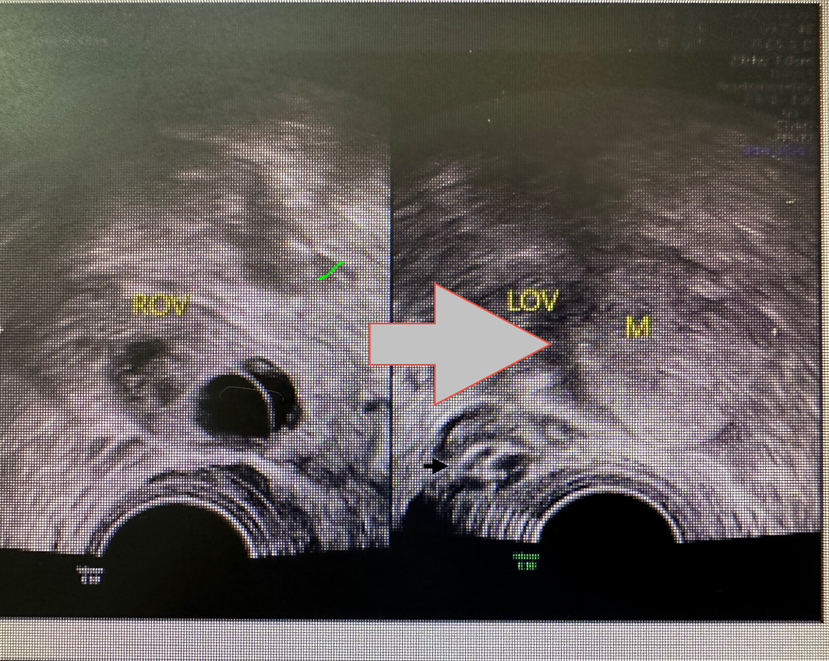

2、影像学提示不典型或可疑恶性:

不管是超声、CT/MRI,如提示肿瘤囊壁增厚有乳头状凸起、实性成分多、血流信号丰富、边界不清等异常信号。必须尽快手术。